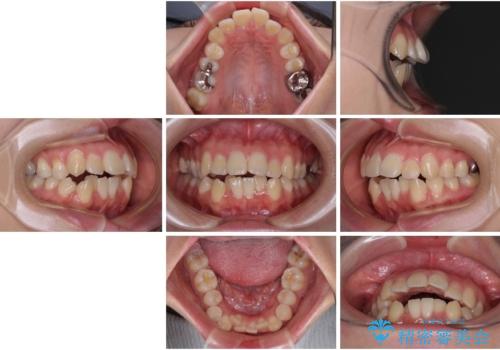

- 下の前歯のデコボコと、口元の突出感を改善したいと来院された患者様です。

突出感の強い上顎前歯をしっかりと後方移動させるため、上顎の裏側の補助装置(リンガルアーチ)とアンカースクリューを併用しています。

上下左右の第一小臼歯を抜歯して、目立ちにくいワイヤー装置で矯正を行いました。